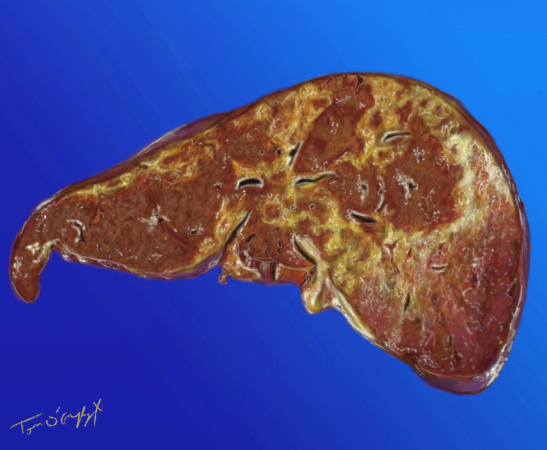

foie en autopsie avec importantes zones de nécrose en lien avec une intoxication au paracetamol

Le paracétamol ou acétaminophène est l’analgésique le plus courant, le plus répandu grâce à ses vertus antipyrétiques. Il est distribué en vente libre. C’est un produit banalisé, qui lui confère, auprès des médecins mais aussi des patients, un caractère de « petit » médicament, à l’image de l’homéopathie. Sauf que son surdosage est toxique pour le foie, et l’intoxication pour des doses pas forcément massives, est létale.